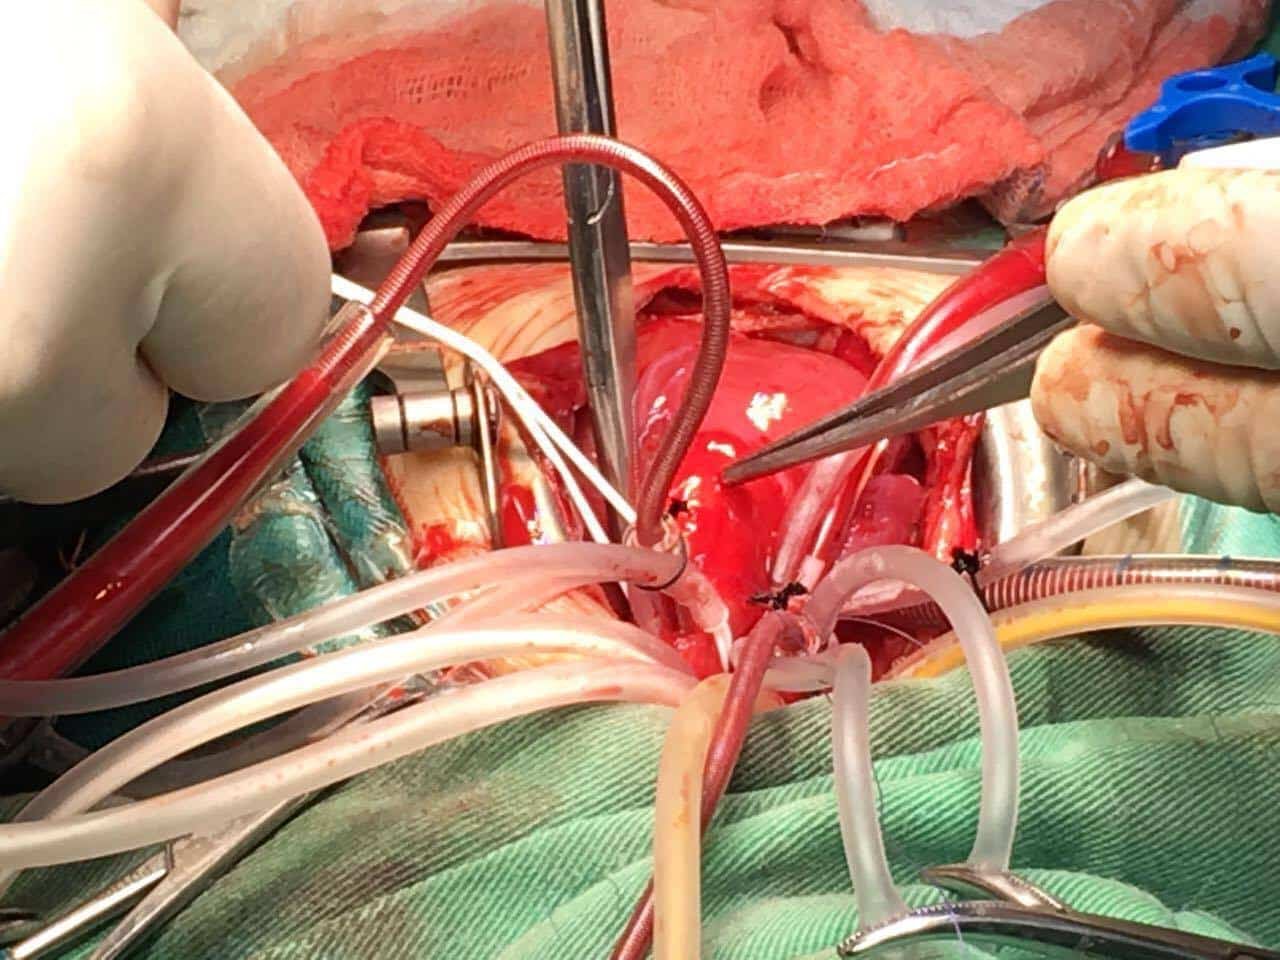

يتم تنويم الطفل عن طريق التخدير الكلى و توصيله بأجهزة التنفس وأجهزة أخرى لمتابعة حالة الطفل ثم بعد ذلك يقوم الطبيب بعمل شق طولي في منتصف الصدر .

1- تقنية استخدام جهاز المضخة القلبية (ماكينة القلب الصناعي )

يساعد جهاز القل بالصناعي في نقل الدم والأكسجين إلى جميع أنحاء الجسم بدلًا من القلب أثناء العملية حيث يكون القلب لا ينبض، وبعد انتهاء العملية يقوم الطبيب بفصل الجهاز ويعود القلب للعمل مرة أخرى كما كان.

- يتم تركيب جهاز المجازة القلبية إذا كانت التقنية المستخدمة في العملية هي تقنية المضخة القلبية.

- يقوم الطبيب بشق عظام الصدر بالكامل باستخدام أدوات طبية معينة.

- يقوم الطبيب بإصلاح المشكلة التي أصابت القلب أو الشرايين.